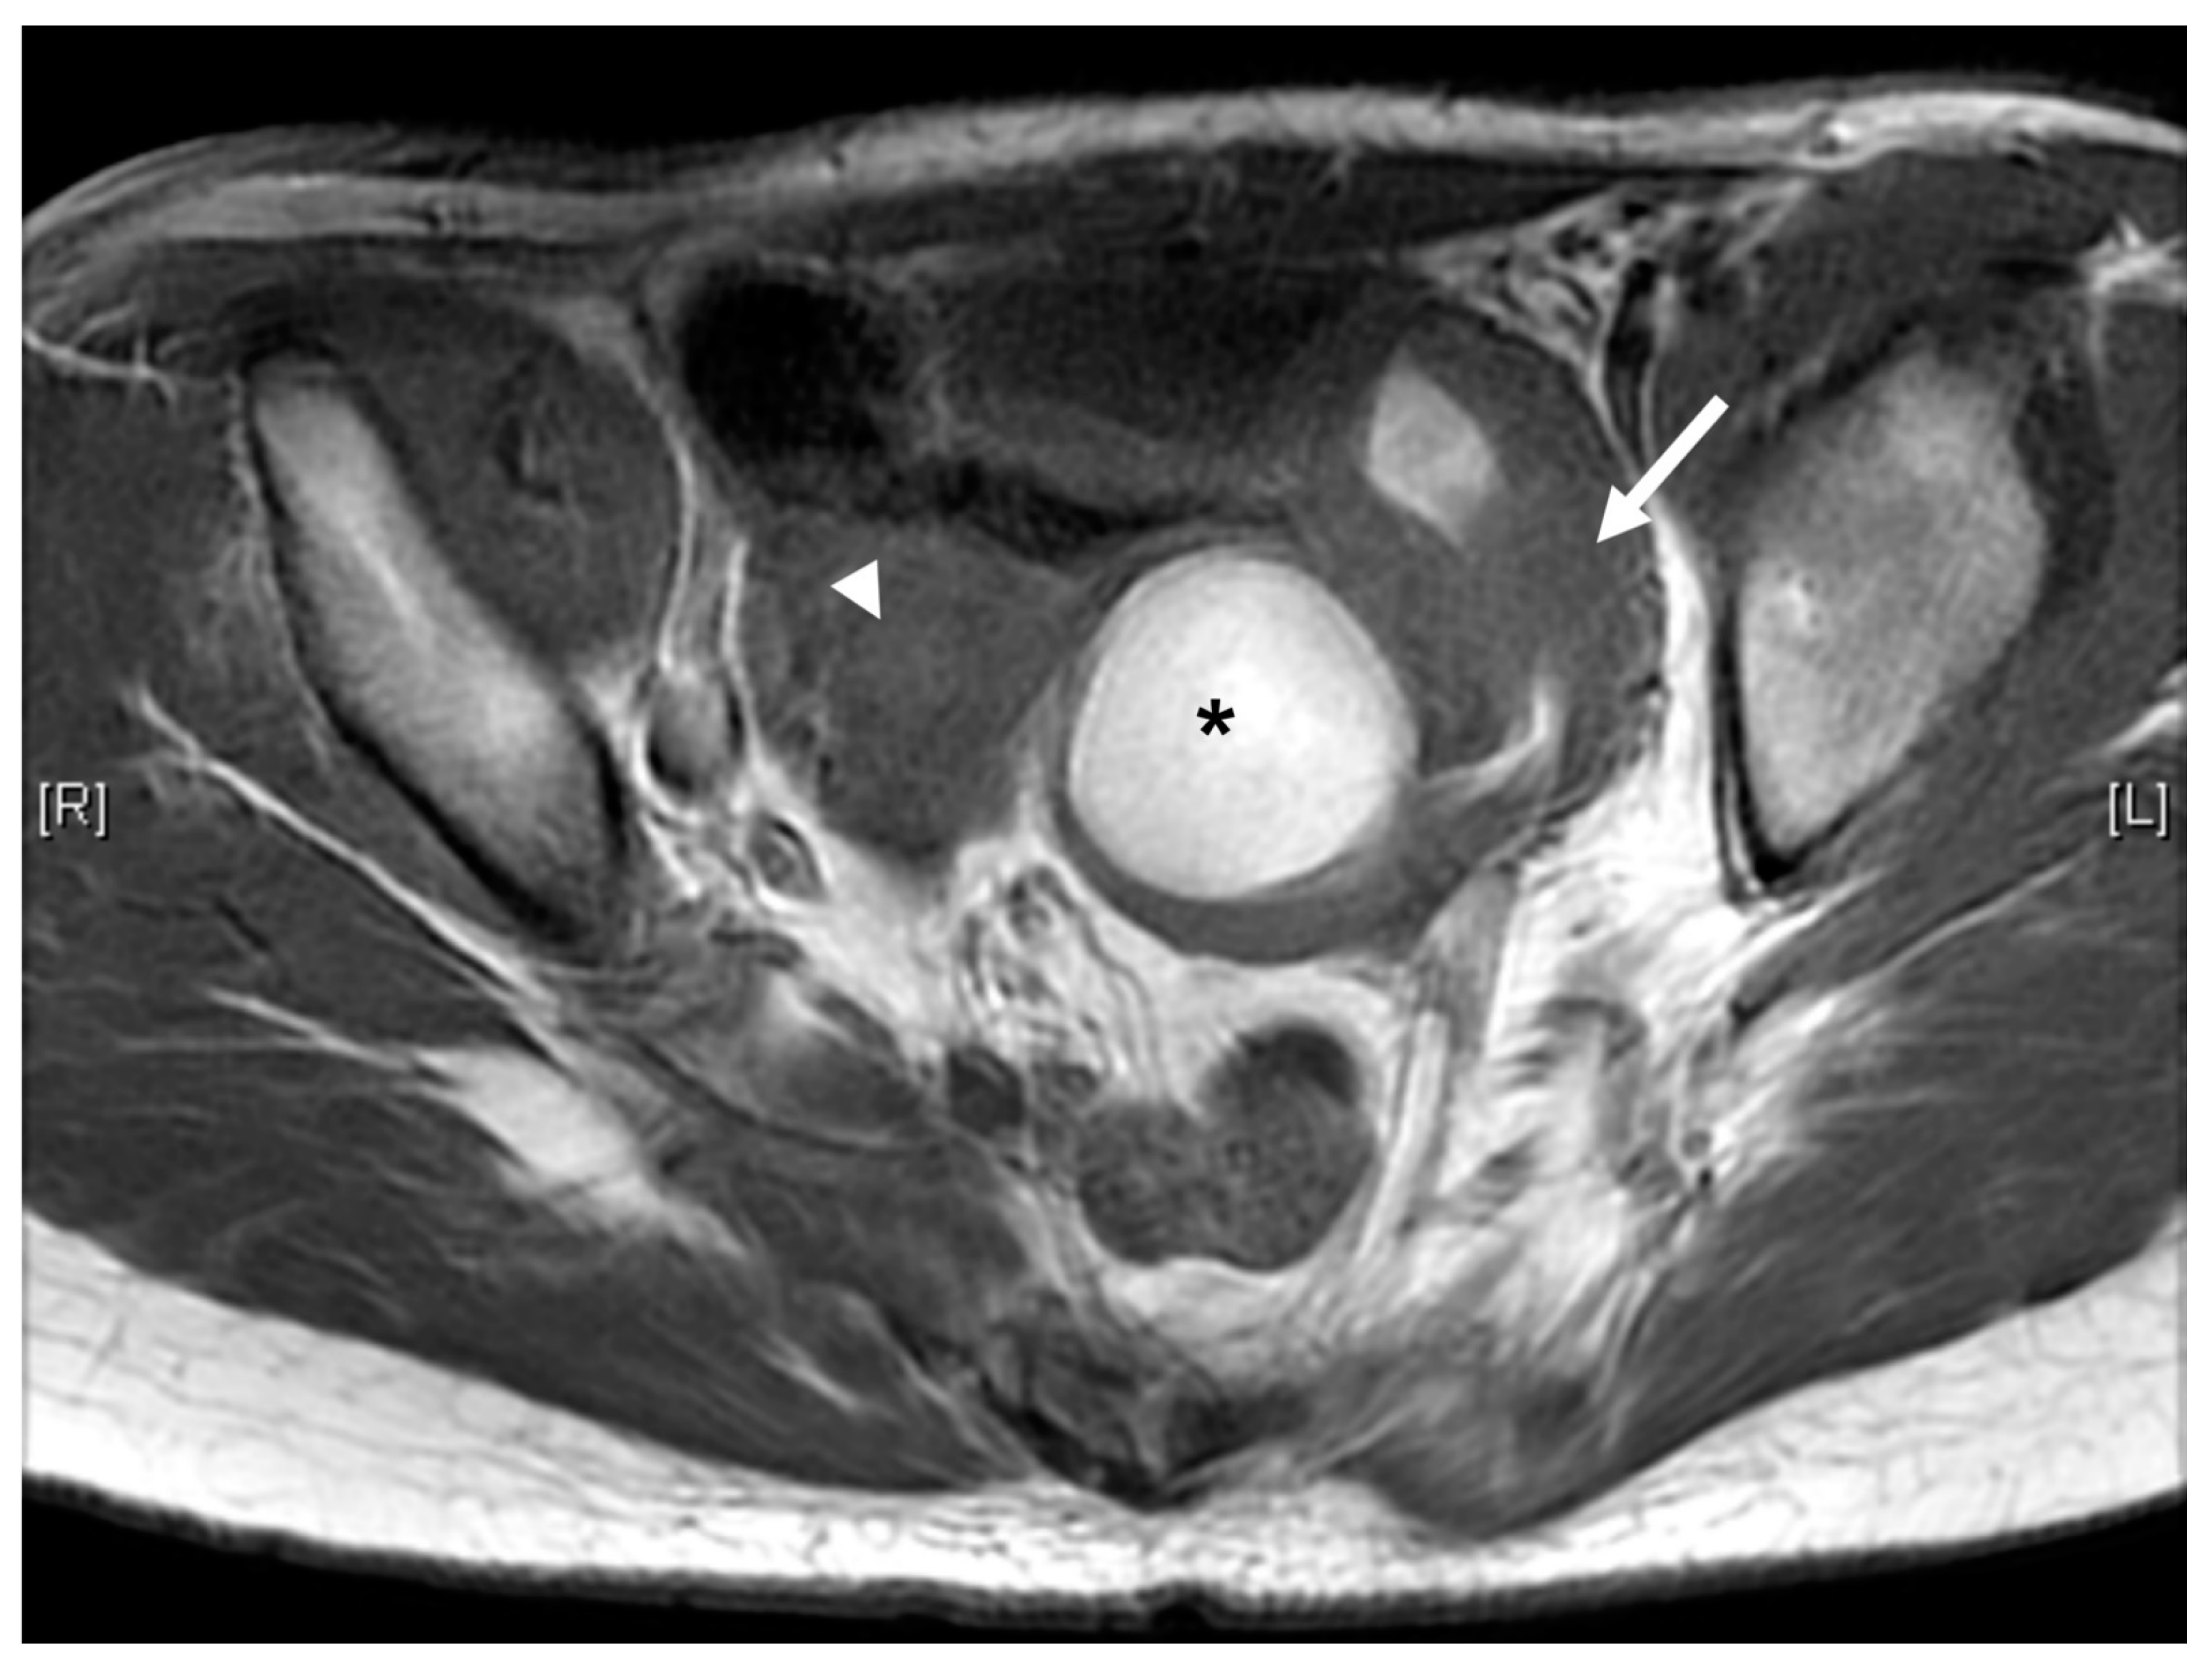

Case 3 was a female infant born at 34 weeks of gestation. The antenatal ultrasound showed fetal ureteral obstruction and oligohydramnios. She had a poorly developed vestibule with a small orifice near the clitoris and high-type imperforate anus, indicating cloacal malformation. A double-barrel colostomy and drainage of 30 mL turbid urine of the orifice of the common channel, possibly from the distended vagina, was performed at 5 hours of age. Abdominal ultrasound at 1 day of age showed a 7.5 cm cystic mass in the lower abdomen, but it decreased in size on the next day. Water instillation via urinary catheter visualized the urinary bladder and enlarged the cystic mass on real-time ultrasound, suggesting HMC with vesicovaginal fistula. The patient received spinal lipoma excision at 8 months of age for the lipomyelomeningocele, and repair for tetralogy of Fallot at 1 year of age. Posterior sagittal anorectovaginourethroplasty using the Pena method was performed at 1 year, 8 months of age, and the distal vagina was replaced by a 5 cm length of rectum. She began menstruating at 12 years, 10 months, which was associated with cyclic abdominal pain, and the MRI detected uterine didelphys with left hematometrocolpos, hemivagina, and left renal agenesis (Figure 4 and Figure 5). Hysteroscopy was performed via the neovagina, and one bulging mass in the left side was observed. The right uterus cavity was normal with smooth endometrium. Herlyn–Werner–Wunderlich syndrome was diagnosed. The patient anticipates left hemi-hysterectomy and transcervical resection of the vaginal septum.

Figure 4.

MRI of case 3: hematometrocolpos (asterisk) and uterine didelphy (arrow and arrowhead).